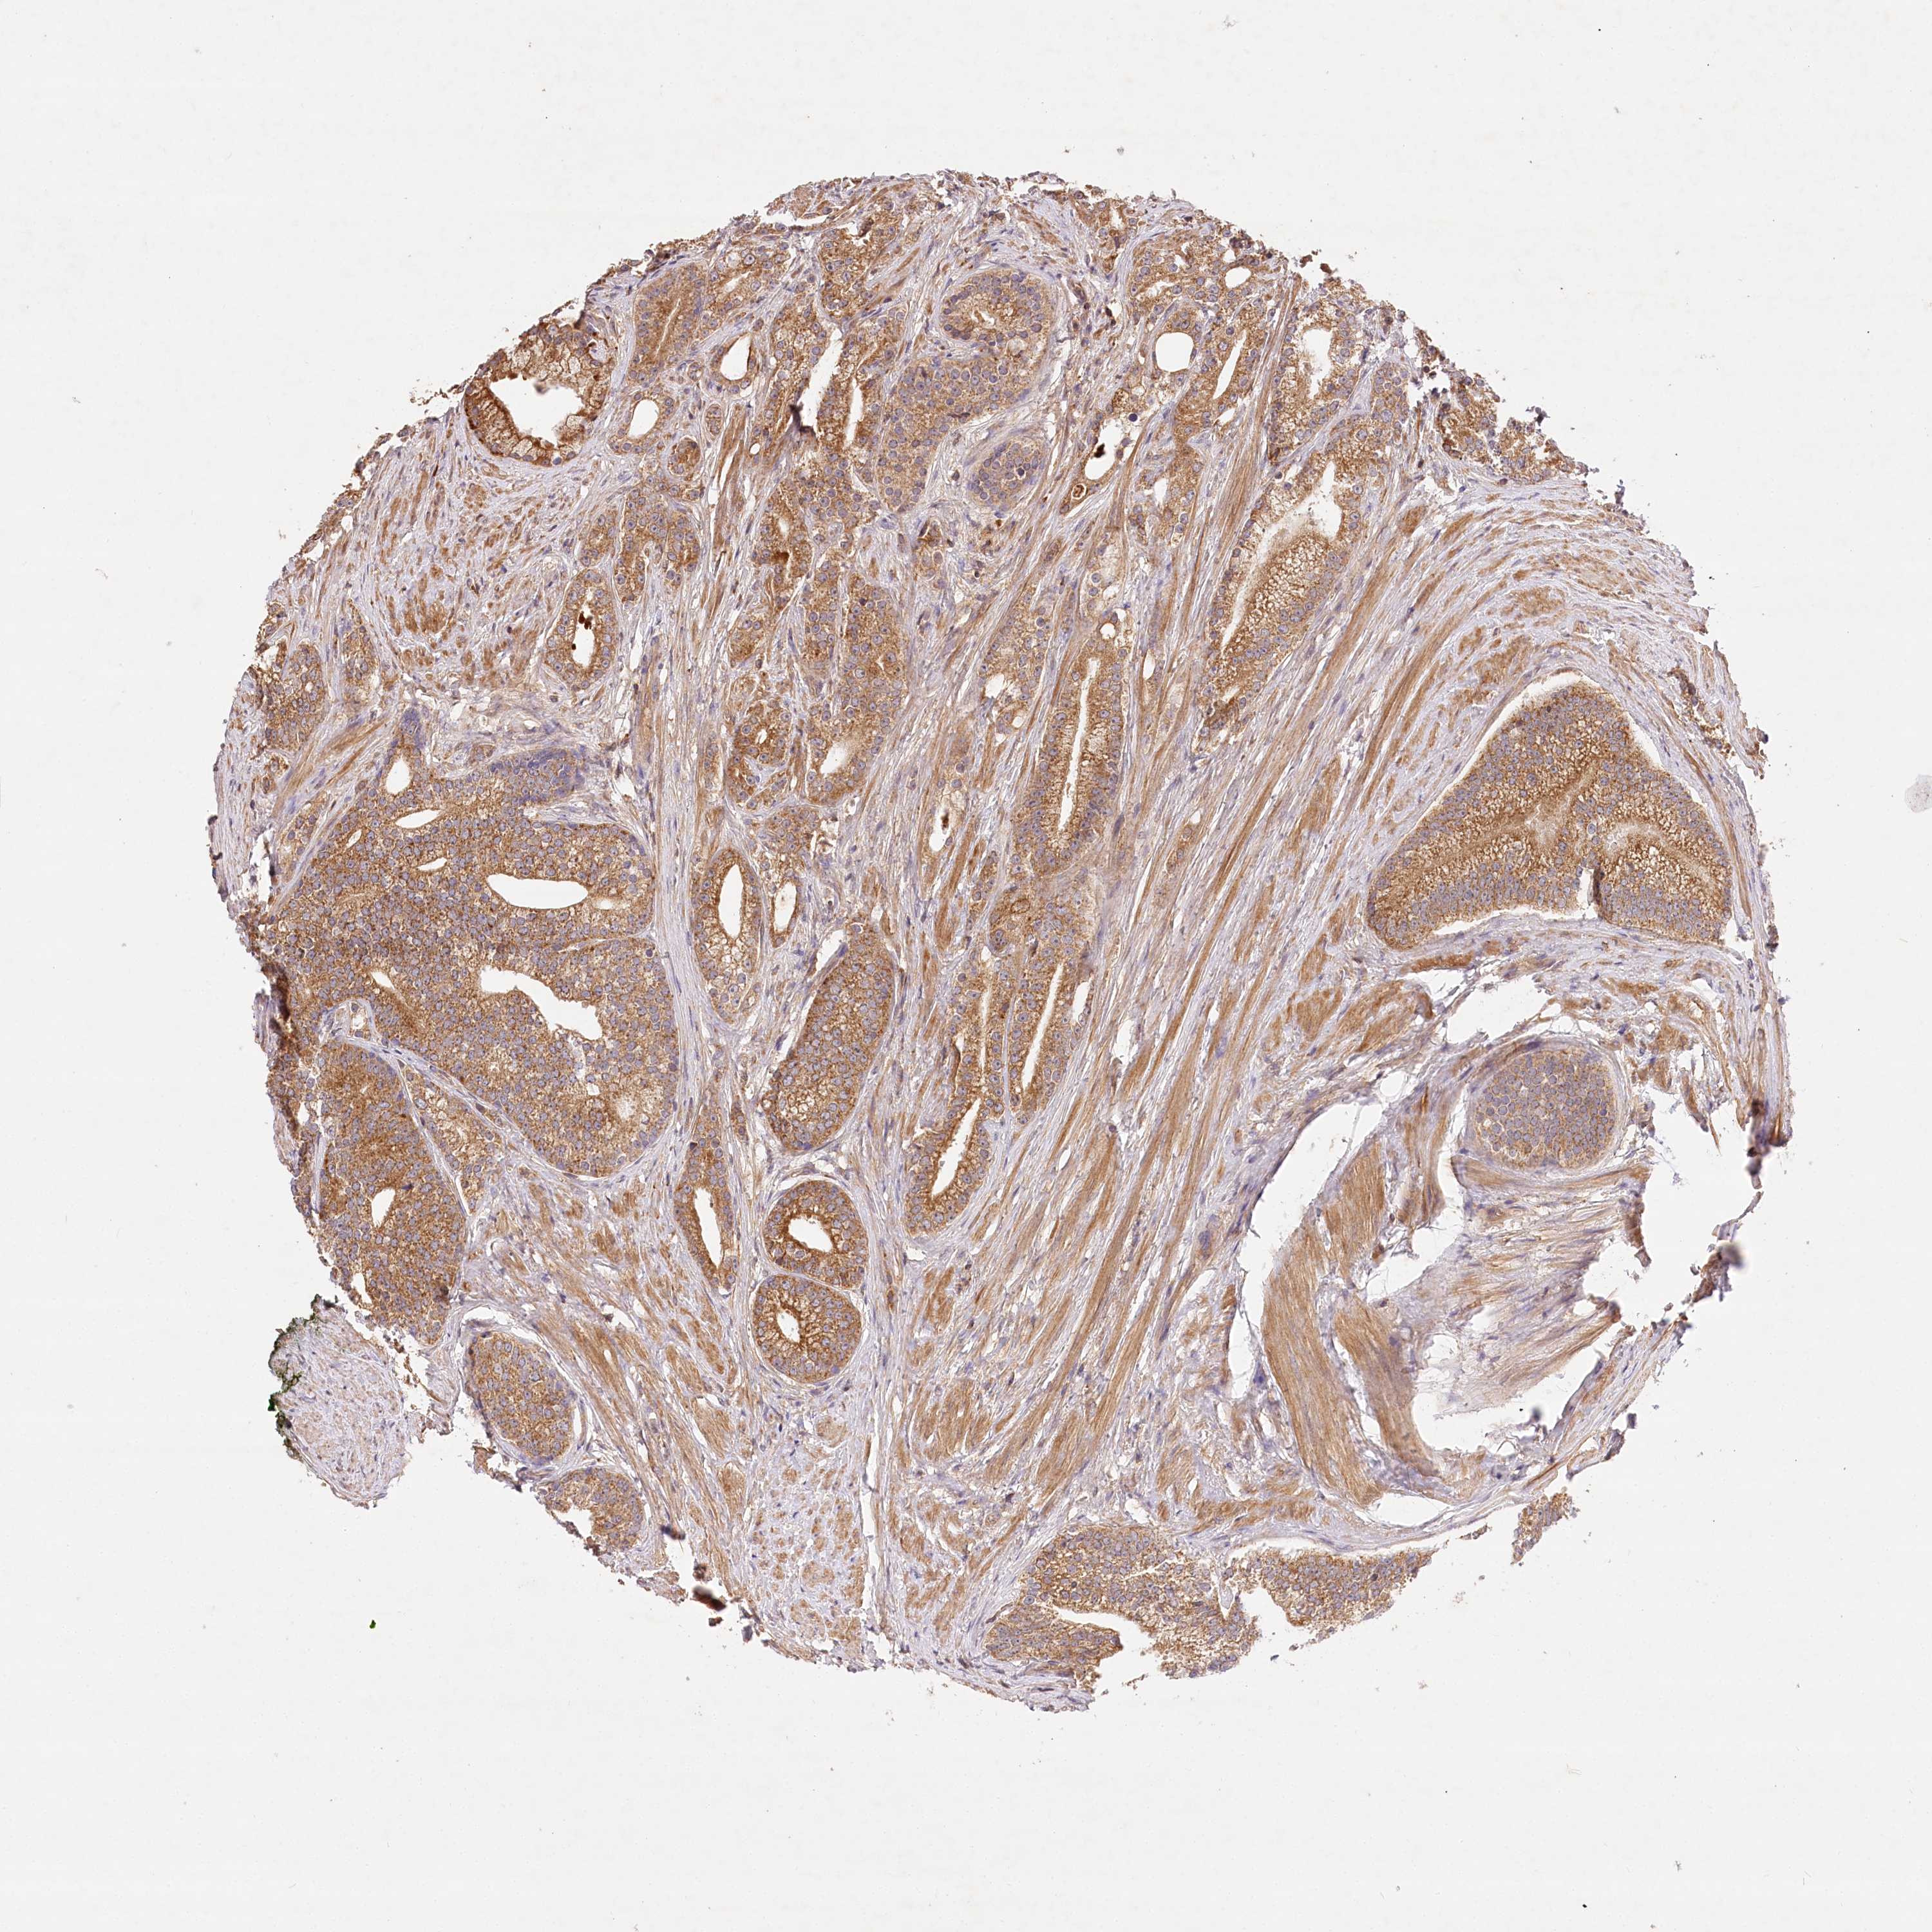

PROSTATE CANCER - Protein expressioni

A mouse-over function shows sample information and annotation data. Click on an image to view it in a full screen mode. Samples can be filtered based on level of antibody staining by selecting one or several of the following categories: high, medium, low and not detected. The assay and annotation is described here.

Antibody stainingi

Antibody staining in the annotated cell types in the current human tissue is reported as not detected, low, medium, or high, based on conventional immunohistochemistry profiling in selected tissues. This score is based on the combination of the staining intensity and fraction of stained cells.

Each image is clickable and will lead to virtual microscopy that enables deeper exploration of all samples and also displays staining intensity scores, fraction scores and subcellular localization as well as patient and tissue information for each sample.

Antibody HPA032060

Antibody HPA032062

Antibody CAB034116

Staining

High

Medium

Low

Not detected

Intensity

Strong

Moderate

Weak

Negative

Quantity

>75%

75%-25%

<25%

None

Location

Nuclear

Cytoplasmic/membranous

Cytoplasmic/membranous,nuclear

Adenocarcinoma, Low grade

Adenocarcinoma, High grade